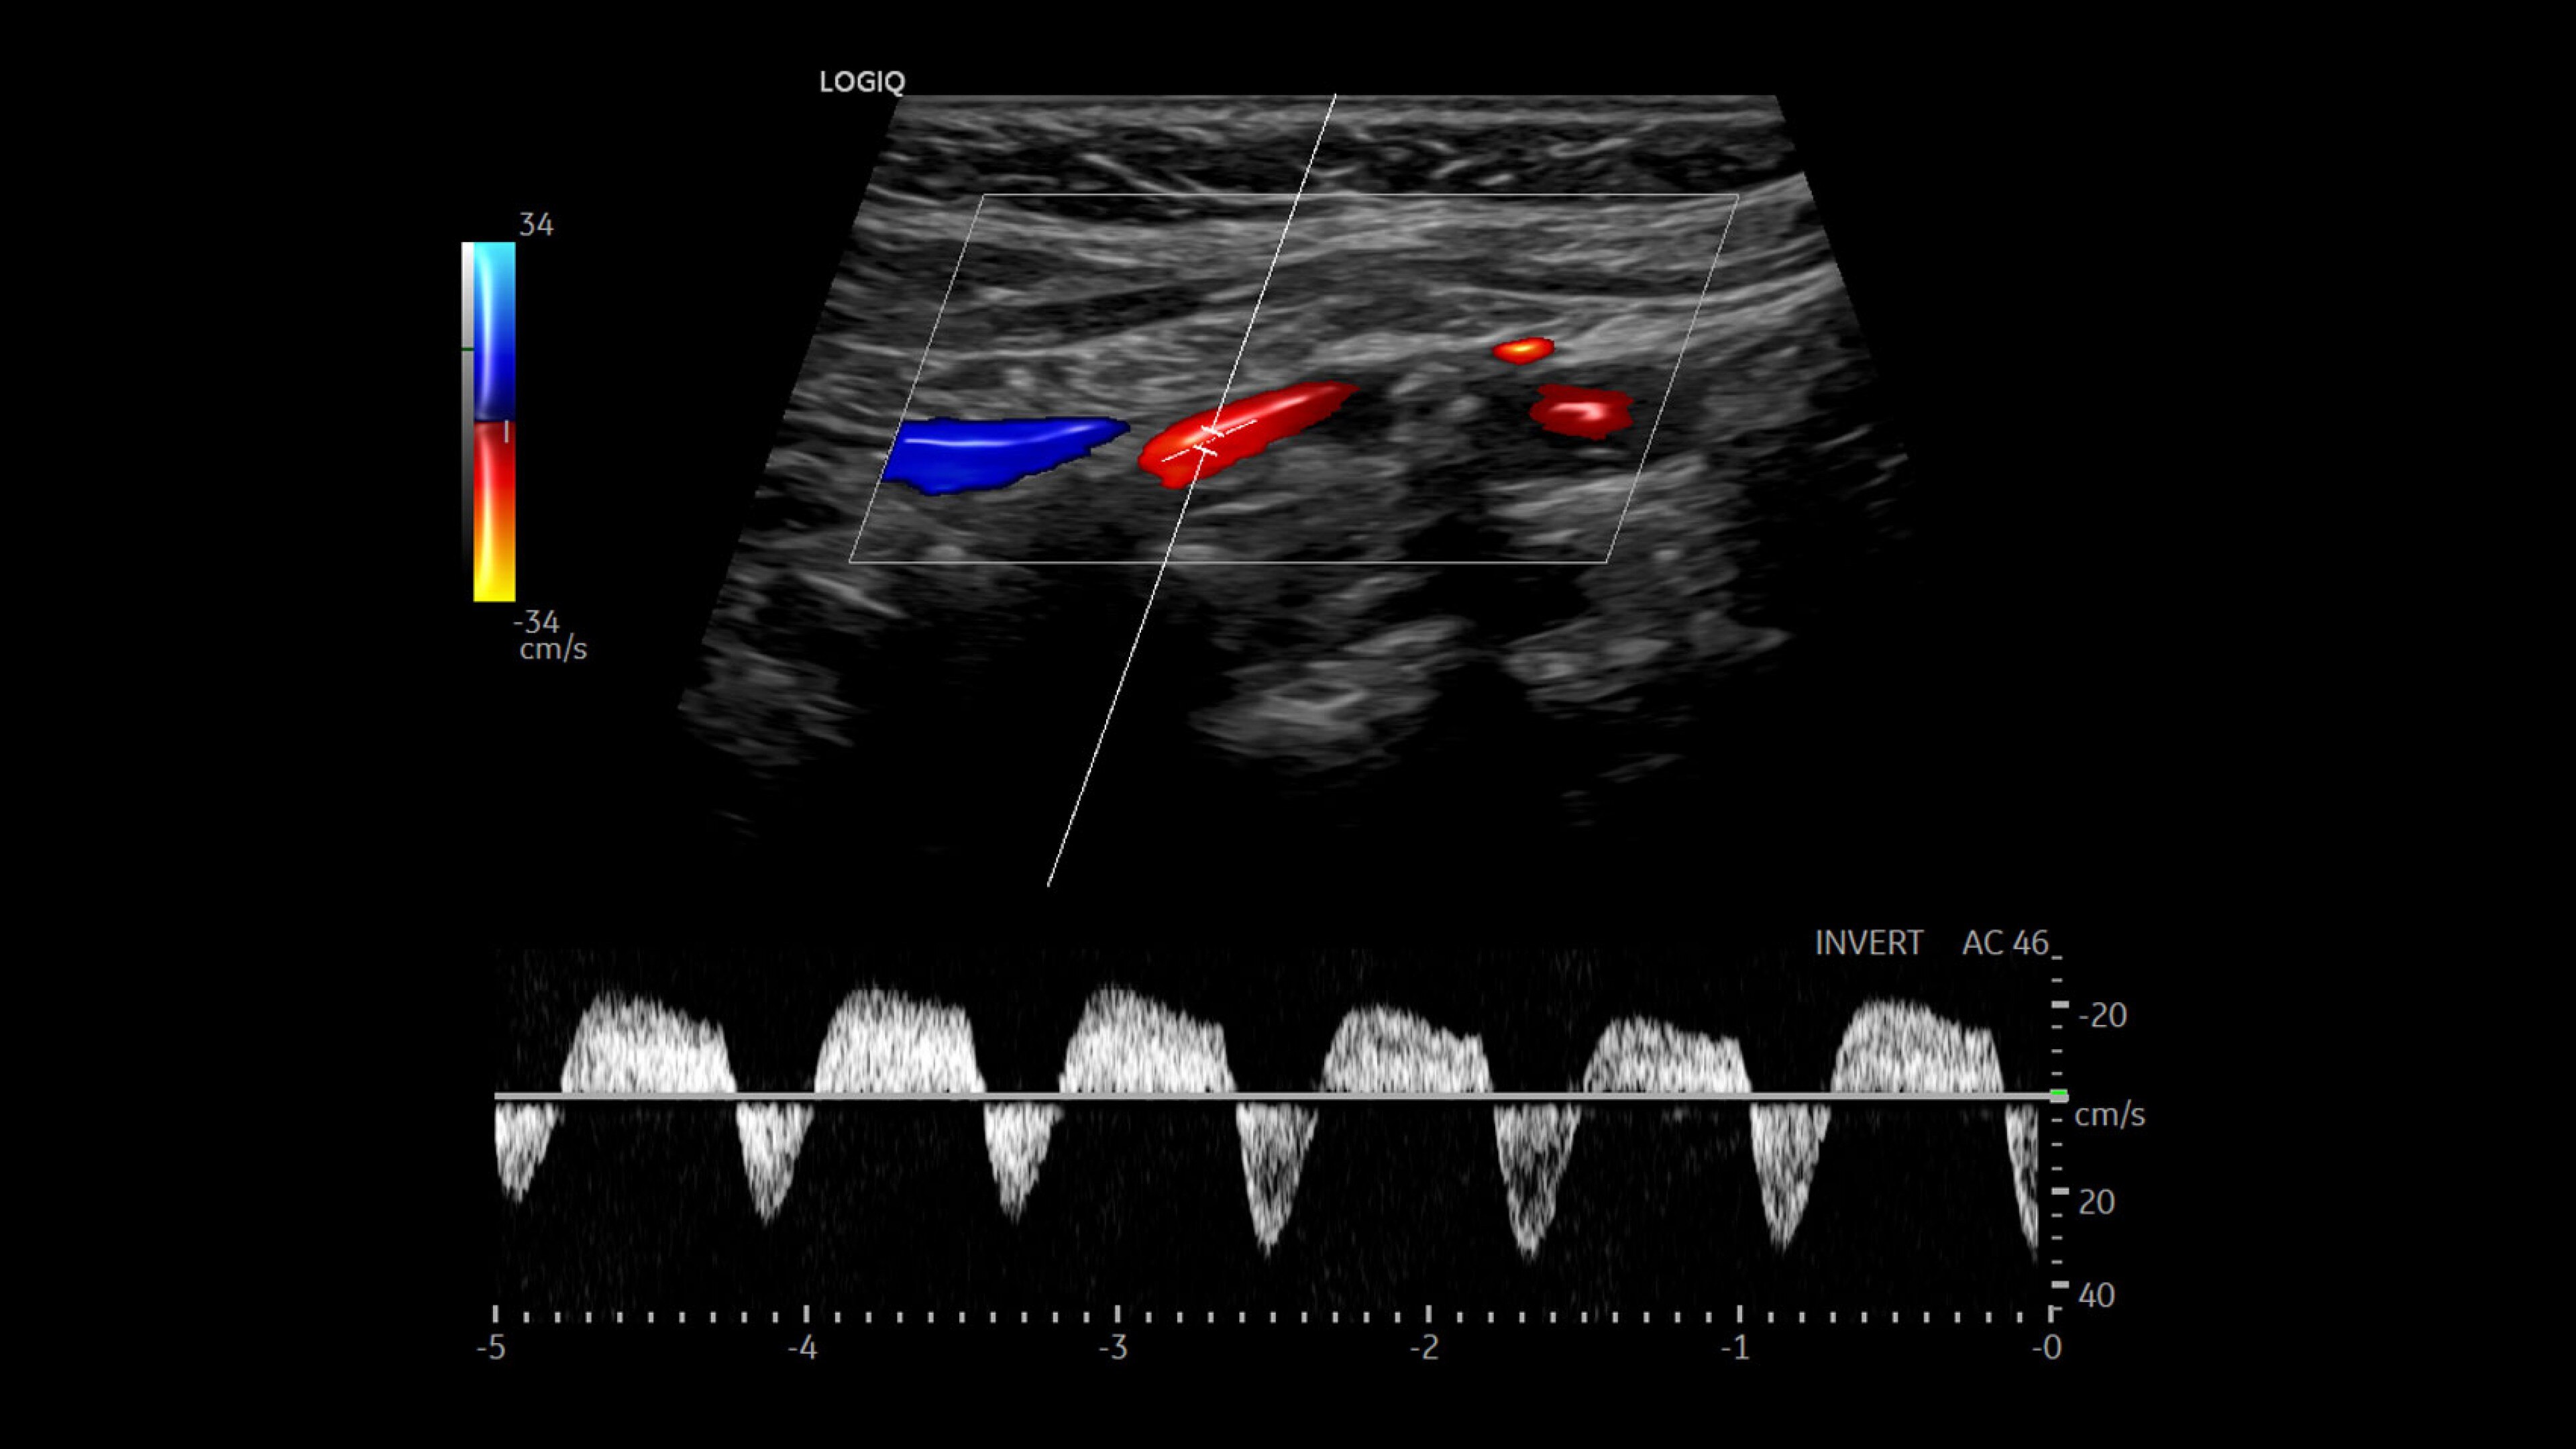

LOGIQ Totus™ Ultrasound

Multi-purpose excellence. Introducing LOGIQ Totus – a head-to-toe, comprehensive ultrasound experience that redefines your expectations.

The LOGIQ Totus™ system is a portable, multi‑purpose, comprehensive solution that combines AI‑powered workflow and decision‑support tools to enhance efficiency and versatility, while its high‑quality imaging supports head‑to‑toe diagnostic confidence.

• Rely on cSound™ Architecture, which delivers exceptional image quality and uniformity

• Leverage a wide range of transducers, including XDclear™, which produces high resolution images covering head-to-toe applications across clinical specialties or care areas

• Address clinically challenging cases with advanced tools such as 2D Shear Wave Elastography, Ultrasound-Guided Attenuation Parameter (UGAP), and Volume Navigation